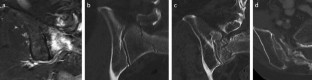

Fig. 1

Fig. 2

Fig. 3

Fig. 4